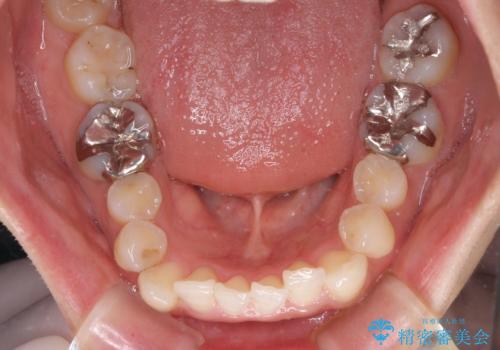

- 口元の突出感と口の閉じにくさを気にして来院された患者様です。

上下左右第一小臼歯4本を抜歯し、ワイヤー装置にて口元を引っ込めるよう矯正治療を行うこととしました。

奥歯が前方に傾斜していることで深く咬みこむ(ディープバイト)状態であったので、なかなか抜歯したスペースが閉じず、様々な方法でディープバイトを改善しながら治療を進めていくこととなりました。